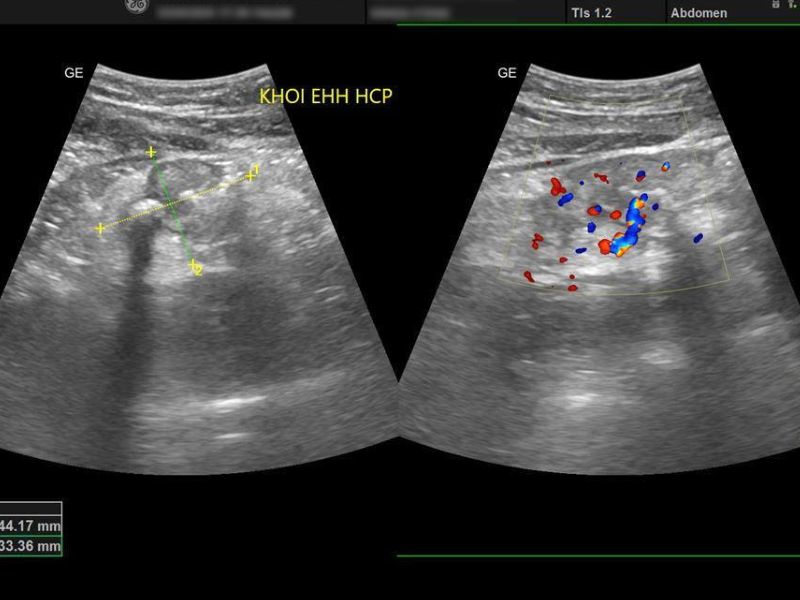

Siêu âm bụng tổng quát là kỹ thuật sử dụng sóng âm tần số cao (thường từ 2–5 MHz đối với khảo sát ổ bụng) để tạo hình ảnh các cơ quan nội tạng theo thời gian thực.

Khi đầu dò phát ra sóng âm, các mô trong cơ thể sẽ phản xạ lại tín hiệu với mức độ khác nhau. Máy siêu âm sẽ xử lý các tín hiệu này và tái tạo thành hình ảnh trên màn hình máy siêu âm.

- Mỗi loại mô có độ phản âm khác nhau

- Từ đó giúp phân biệt cấu trúc bình thường và bất thường.